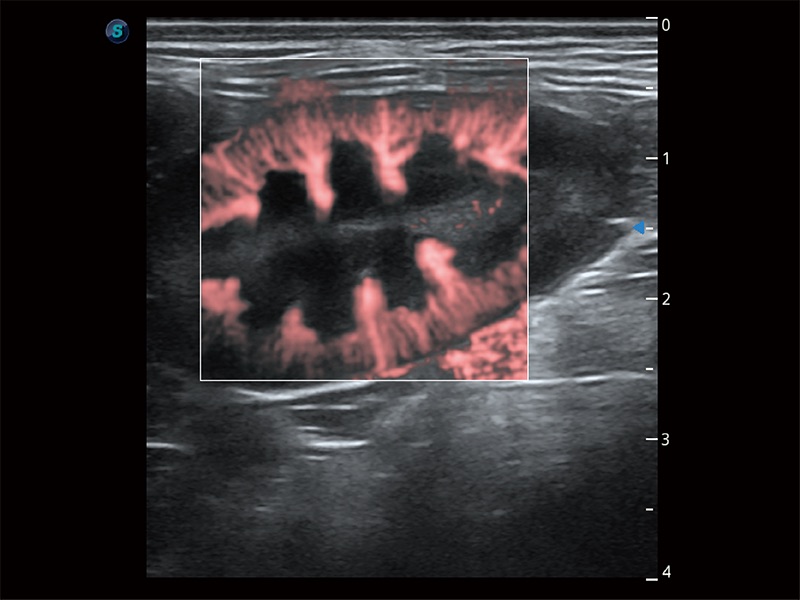

(犬)胎儿主动脉弓立体血流

• Bright Flow 立体血流成像

在传统二维血流成像的基础上,呈现血流的立体感,具有动感的生命力之美。即便是微小的血管也能轻松应对,提高了血流的视觉敏感性。